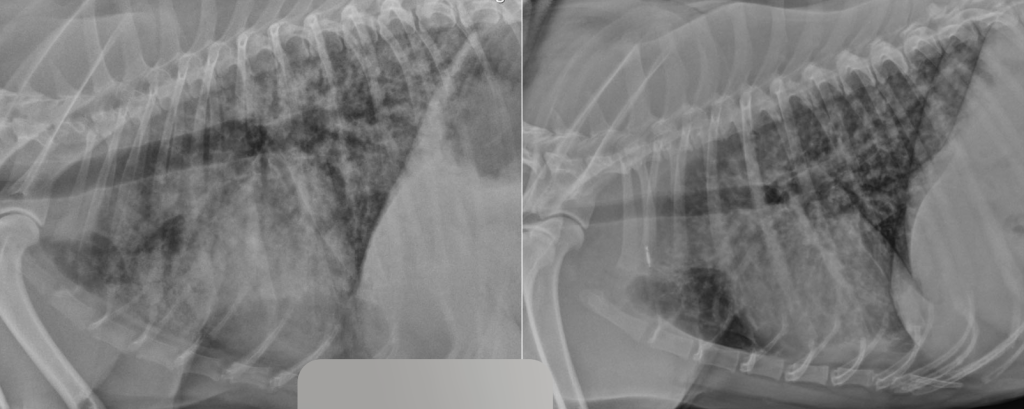

На пятые сутки, спустя двое суток после операции, общее состояние пациента и результаты анализов крови улучшились, активность увеличилась, собака стала более эмоциональной, но самостоятельный аппетит по-прежнему отсутствовал. Диарея не наблюдалась, жажда и мочеиспускание оставались без особенностей. Болезненность брюшной стенки оценивалась как легкая. Были отменены мультимодальная анальгезия, поддерживающая инфузионная терапия и смекта. Однако появились новые симптомы: кашель и увеличение частоты дыхательных движений во сне до 30 дых. дв./мин, без признаков диспноэ. Уровень насыщения крови кислородом (SpO2) без дополнительной оксигенотерапии составлял 93–95%. При рентгенологическом исследовании были выявлены преимущественно диффузные альвеолярные затемнения легочной ткани, охватывающие почти все поля легких. Наибольшая площадь поражения наблюдалась в каудальных долях обоих легких (рис. 9). Данные изменения в совокупности с установленным диагнозом указывали на высокую вероятность геморрагий в легочной паренхиме как одного из проявлений лептоспироза.

Синдром лептоспирозного легочного кровотечения (англ. leptospiral pulmonary haemorrhage syndrome; LPHS) является тяжелым проявлением острого лептоспироза и в последние годы все чаще диагностируется у собак и других видов животных14. Гистопатологические поражения легочной ткани при LPHS имеют схожие характеристики у разных видов и проявляются различной степенью внутриальвеолярного кровоизлияния при отсутствии выраженного воспалительного клеточного инфильтрата или васкулита. Внутриальвеолярный отек, фибрин и гиалиновые мембраны, характерные для патологий с диффузным альвеолярным повреждением (например, острый респираторный дистресс-синдром; ОРДС), также могут наблюдаться при LPHS, но не являются доминирующими признаками15. Патогенетические механизмы LPHS плохо изучены. В настоящее время исследуются несколько гипотез, включая системные воспалительные, иммуноопосредованные и прямые эффекты, вызываемые лептоспирами. Внутриальвеолярное кровоизлияние может быть обнаружено даже у собак без явных респираторных признаков17. Это указывает на то, что LPHS может быть более распространенным у собак с лептоспирозом, чем принято считать. Рентгенографические изменения, указывающие на LPHS, обычно первоначально проявляются в каудодорсальных отделах легочных полей и, как правило, носят двусторонний и недолевой характер. Поражения варьируются от легкого интерстициального рисунка до легкого или тяжелого ретикулонодулярного легочного рисунка с очаговыми альвеолярными инфильтратами. У некоторых собак наблюдается небольшое количество плеврального выпота (рис. 10). Рентгенографические изменения могут присутствовать даже при отсутствии клинических признаков респираторных нарушений26.